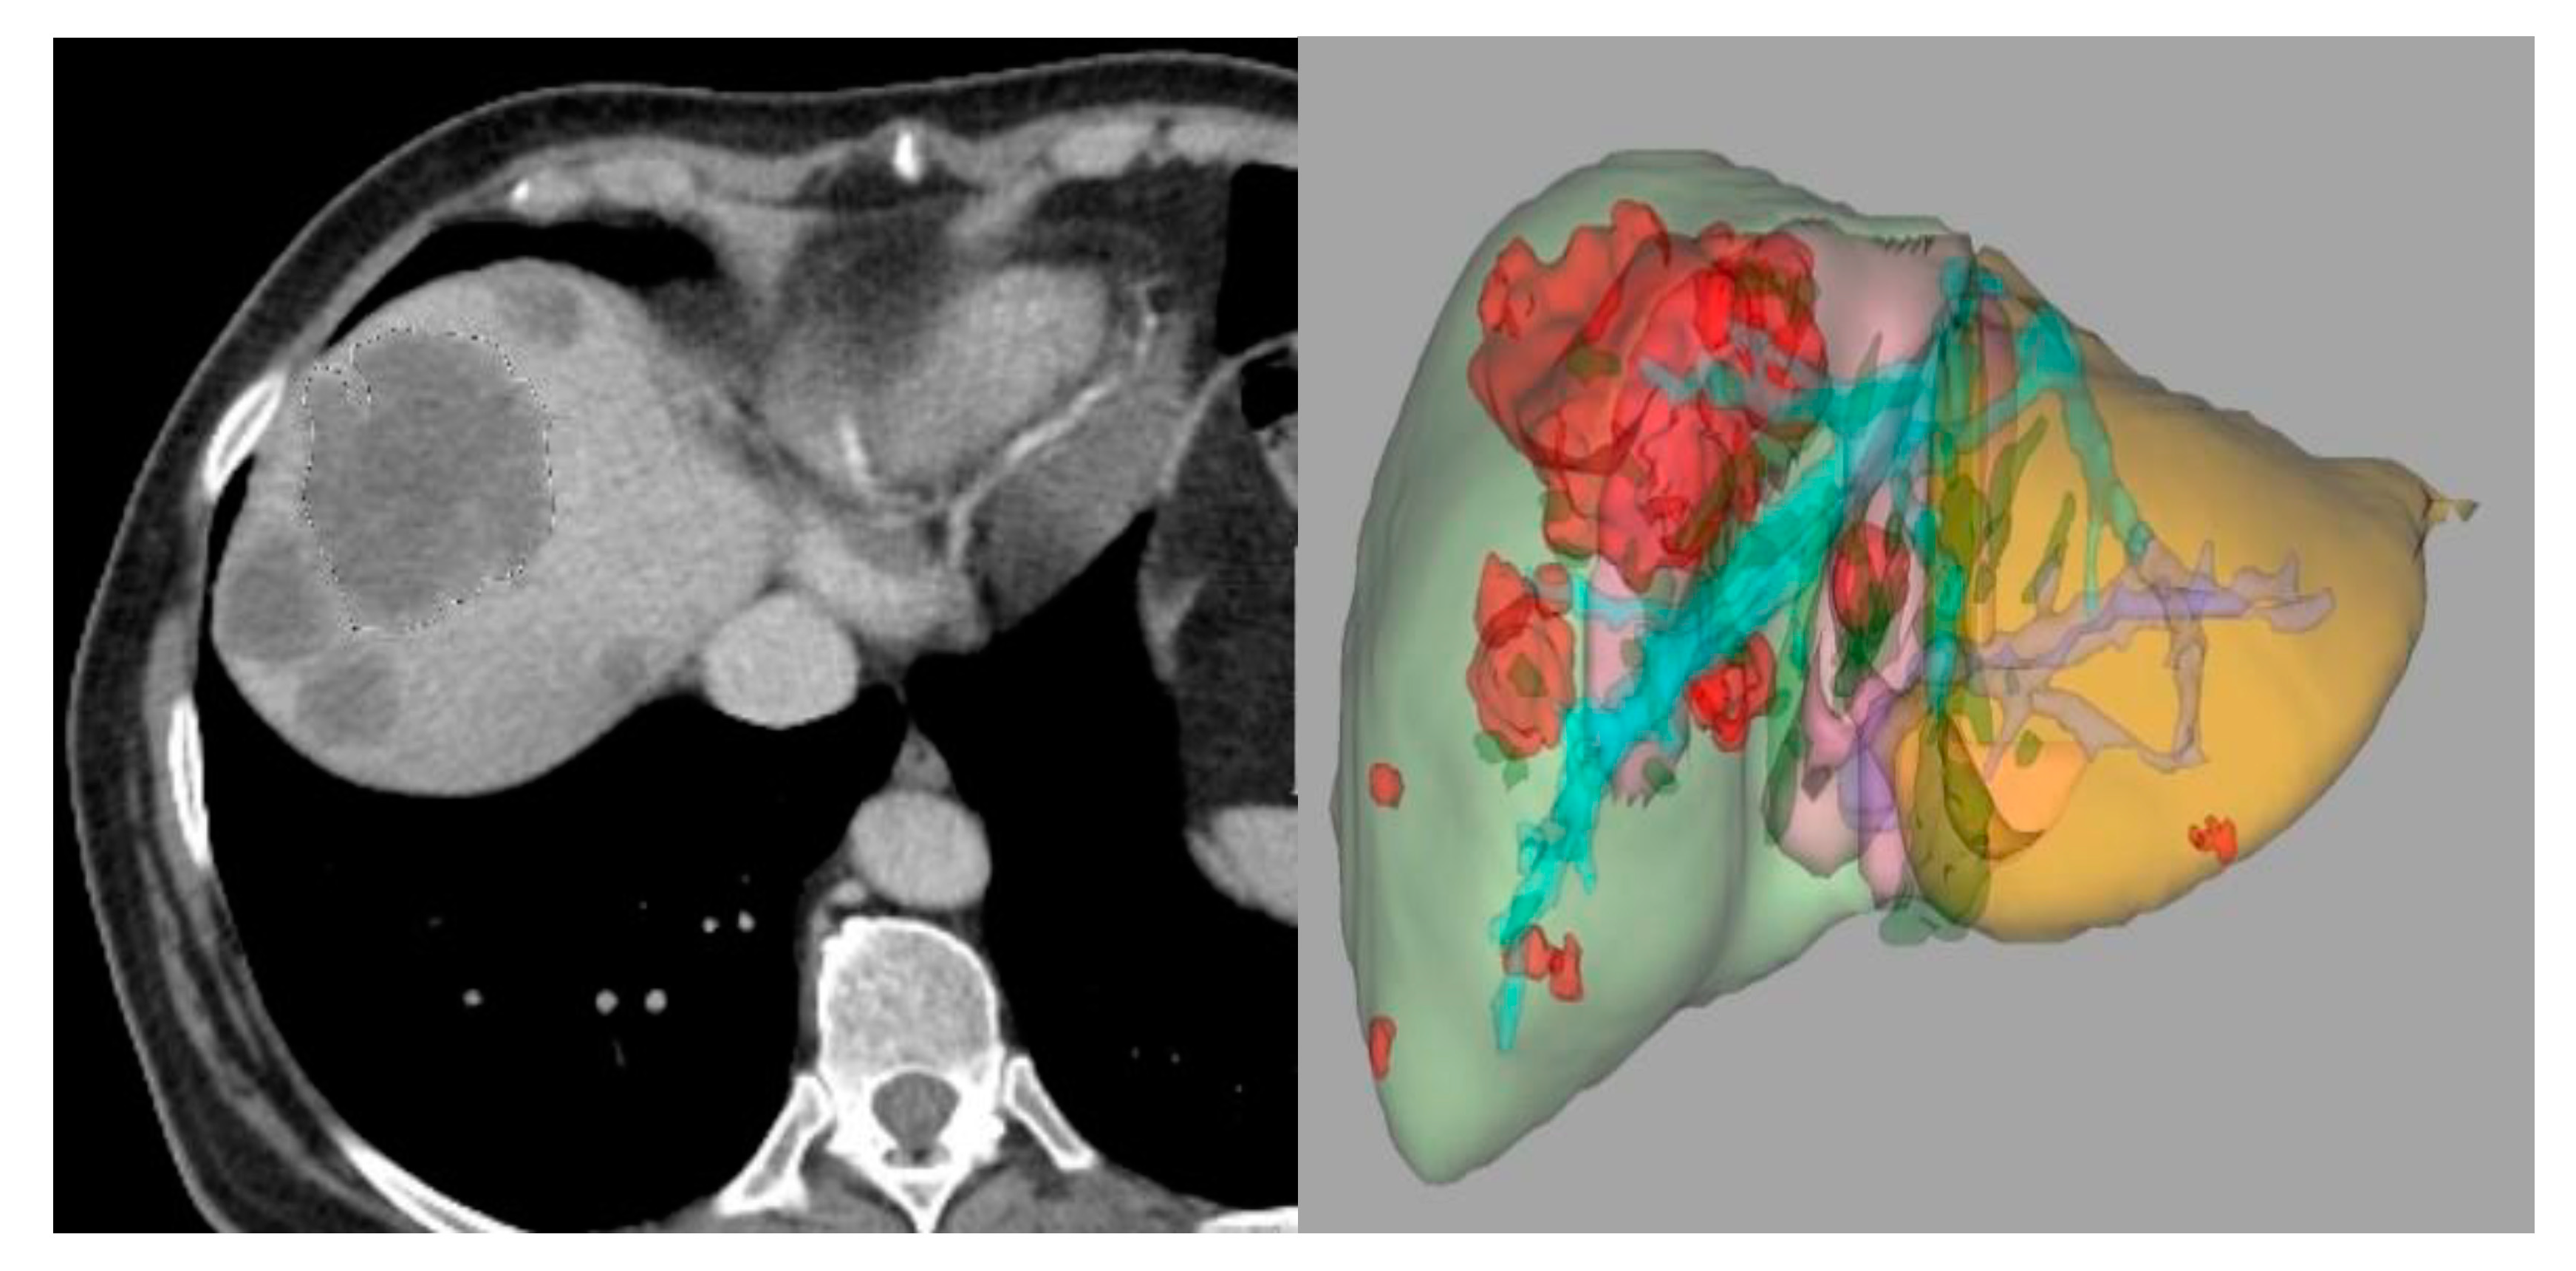

3.2.3. Segmentation

In this phase, the parts of the image that were considered of interest (called “regions of interest” or ROIs) are separated from the rest of the image and the data of these relevant segments are obtained [40,41]. The delineation of this ROI can be conducted manually, semi-automatically, or automatically, in 2D or 3D. This is a critical phase because many tumors can have edges indistinguishable from normal tissues, and the data obtained in this phase can experience variations [40]. Manual segmentation is more laborious and presents greater interobserver variability, on the other hand, in tumor pathology it is often almost the only alternative due to how poorly delimited the lesion usually is. Manual segmentation is usually performed by the radiologist in a slice-by-slice manner, and the ideal is to include the highest percentage of the lesion in the study [40,41]. It is considered the gold standard, but it requires a considerable investment of time. Currently, there are very refined semi-automatic 3D-segmentation tools (Figure 4), which allow segmentation through artificial intelligence guided by the radiologist himself. In this way, in a few seconds, the entire tumor volume in the segmented region can be included in a supervised way. Automatic segmentation in oncology has a limited application because the heterogeneity and the poorly differentiated borders of many tumors mean that the segmentation usually includes areas in the de ROI where there is no tumor, with the consequences that this would entail in the extraction of features [41].

Figure 4.

Three-dimensional semi-automatic segmentation of liver metastases of colorectal cancer.